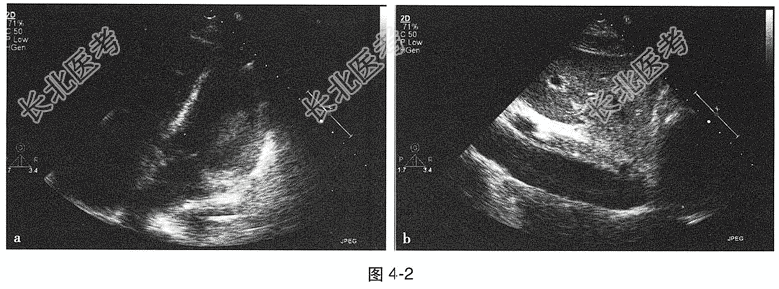

- 多项选择题2.[提示]实验室检查:ALT 387IU/L, AST 209IU/L,肾功能、血生化学指标、空腹血糖正常。TNI 1.6ng/ml(0~0.06ng/ml)、NT-proBNP 5573pg/ml。心肌酶谱: CK-MB 190.5ng/ml(0.3~4ng/ml)、CK 5669IU/L(30~135IU/L),LDH 3358IU/L(313~618IU/L), PCT0.565ng/ml。血气分析:pH 7.38, PaO₂ 68mmHg,PaCO₂ 42mmHg。心电图: 见图4-1。甲状腺功能正常,风湿系列(-)。超声心动图: 左心室扩大,心室室壁运动普遍减弱, LVEF 35%,肺动脉压轻度升高38mmHg, 下腔静脉增宽,见图4-2。患者反复出现胸闷、气短、阵发性呼吸困难, 进食差、尿量少。初步诊断为